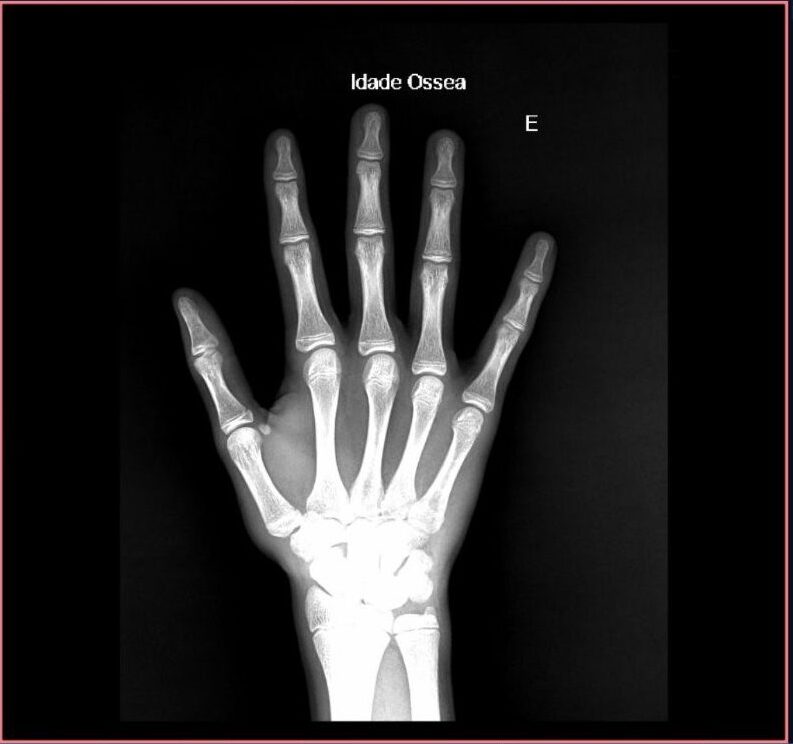

Cálculo de idade óssea com IA no raio-x de mãos e punhos

Ferramentas com esse foco são capazes de estimar a maturidade óssea de um indivíduo baseando-se nas dimensões apresentadas na imagem de raio-x de mãos e punhos.

A análise de idade óssea é especialmente relevante em áreas relacionadas à pediatria. Neste caso, o algoritmo de cálculo tem mais relevância como base de suporte ao diagnóstico do médico responsável.